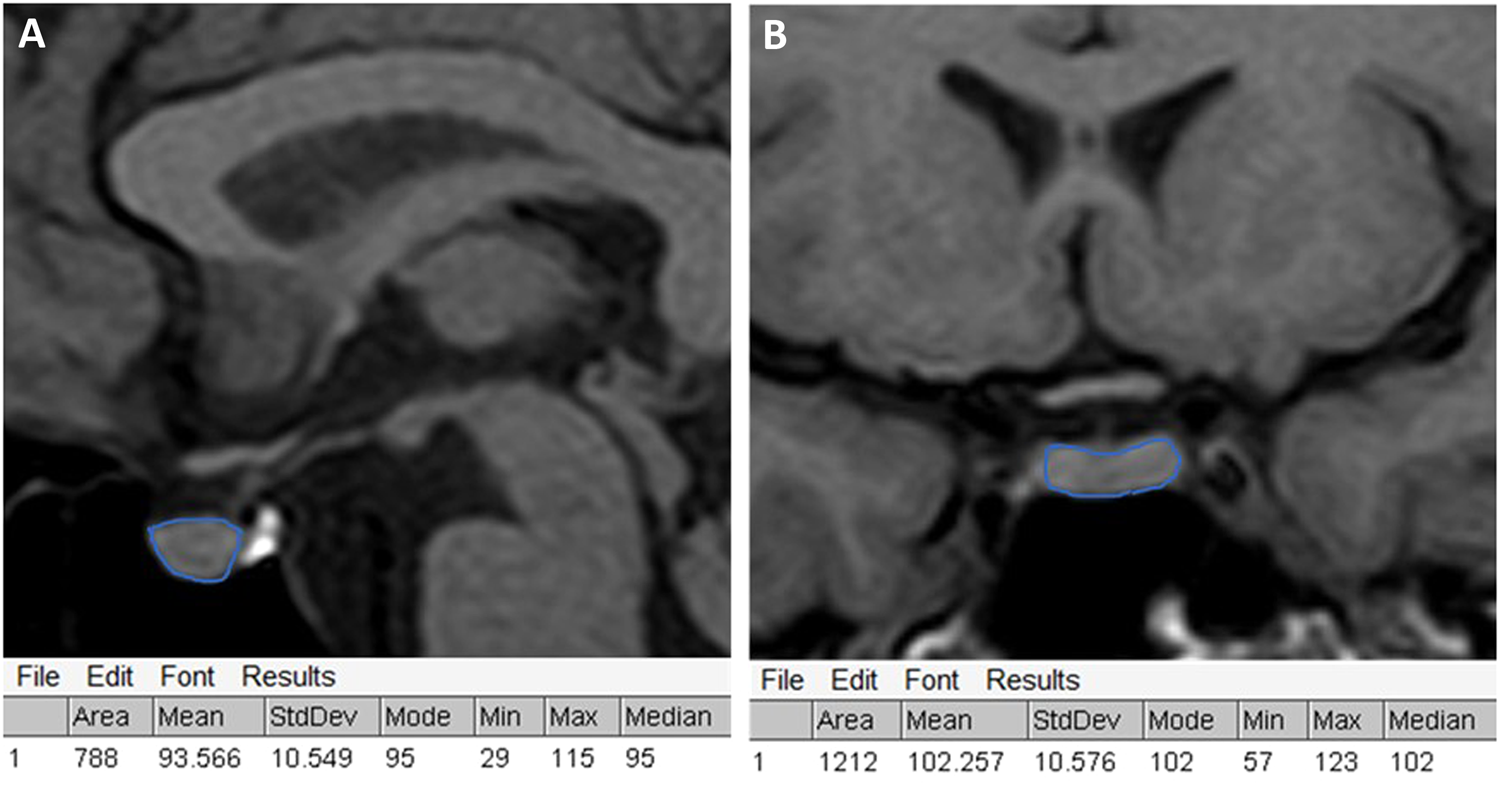

Example of marking the region of interest in coronal (A) and sagittal (B) pituitary RM scans and results of the image analysis using ImageJ software.